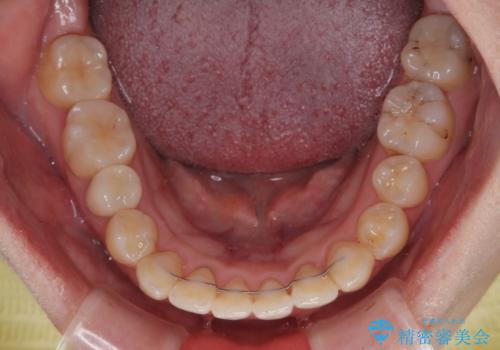

矯正治療後は全顎的にむし歯が多いため、セラミッククラウンやインレーにより補綴治療を行うこととしました。

急速拡大が奏効し、非抜歯矯正にて八重歯を解決することができました。

矯正治療後半で結婚式を挙げられたそうですが、参列された方々からは綺麗に整った前歯に大変驚かれたそうで、非常に満足されていらっしゃいました。